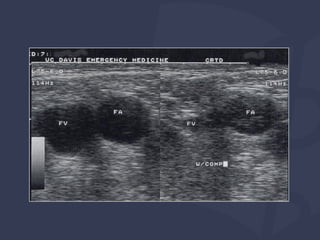

Identificação de artéria vs veia na ultrassonografia

Chave para o sucesso!

VEIAS SÃO:

Compressível

Parede fina e irregular em comparação com a artéria

Não pulsátil (IJ pode ter ondas trifásicas)

Varia com a respiração

Durante a "Análise inicial", observe o

seguinte:

⦿ Patência

⦿ Anatomia local

⦿ Tamanho (<5 mm complicado)

⦿ Trombo presente?

Técnica

Interpretação de imagens Identificaçãode artéria vs veia na ultrassonografia Chave para o sucesso! VEIAS SÃO: Compressível Parede fina e irregular em comparação com a artéria Não pulsátil (IJ pode ter ondas trifásicas) Varia com a respiração

Durante a "Análiseinicial", observe o seguinte: ⦿ Patência ⦿ Anatomia local ⦿ Tamanho (<5 mm complicado) ⦿ Trombo presente? Técnica